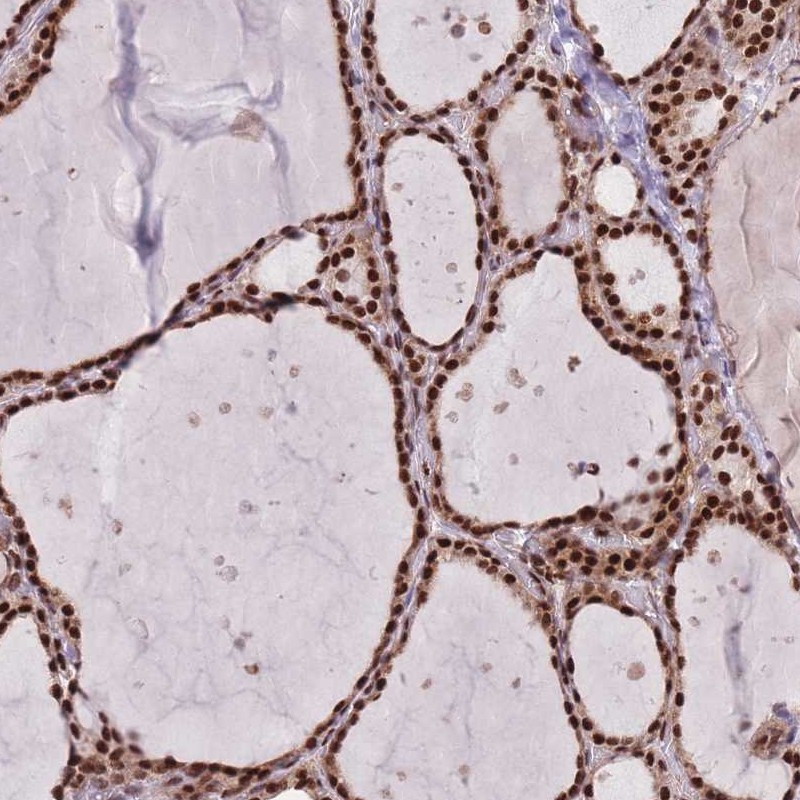

Immunohistochemical staining of human thyroid gland shows nuclear positivity in glandular cells.